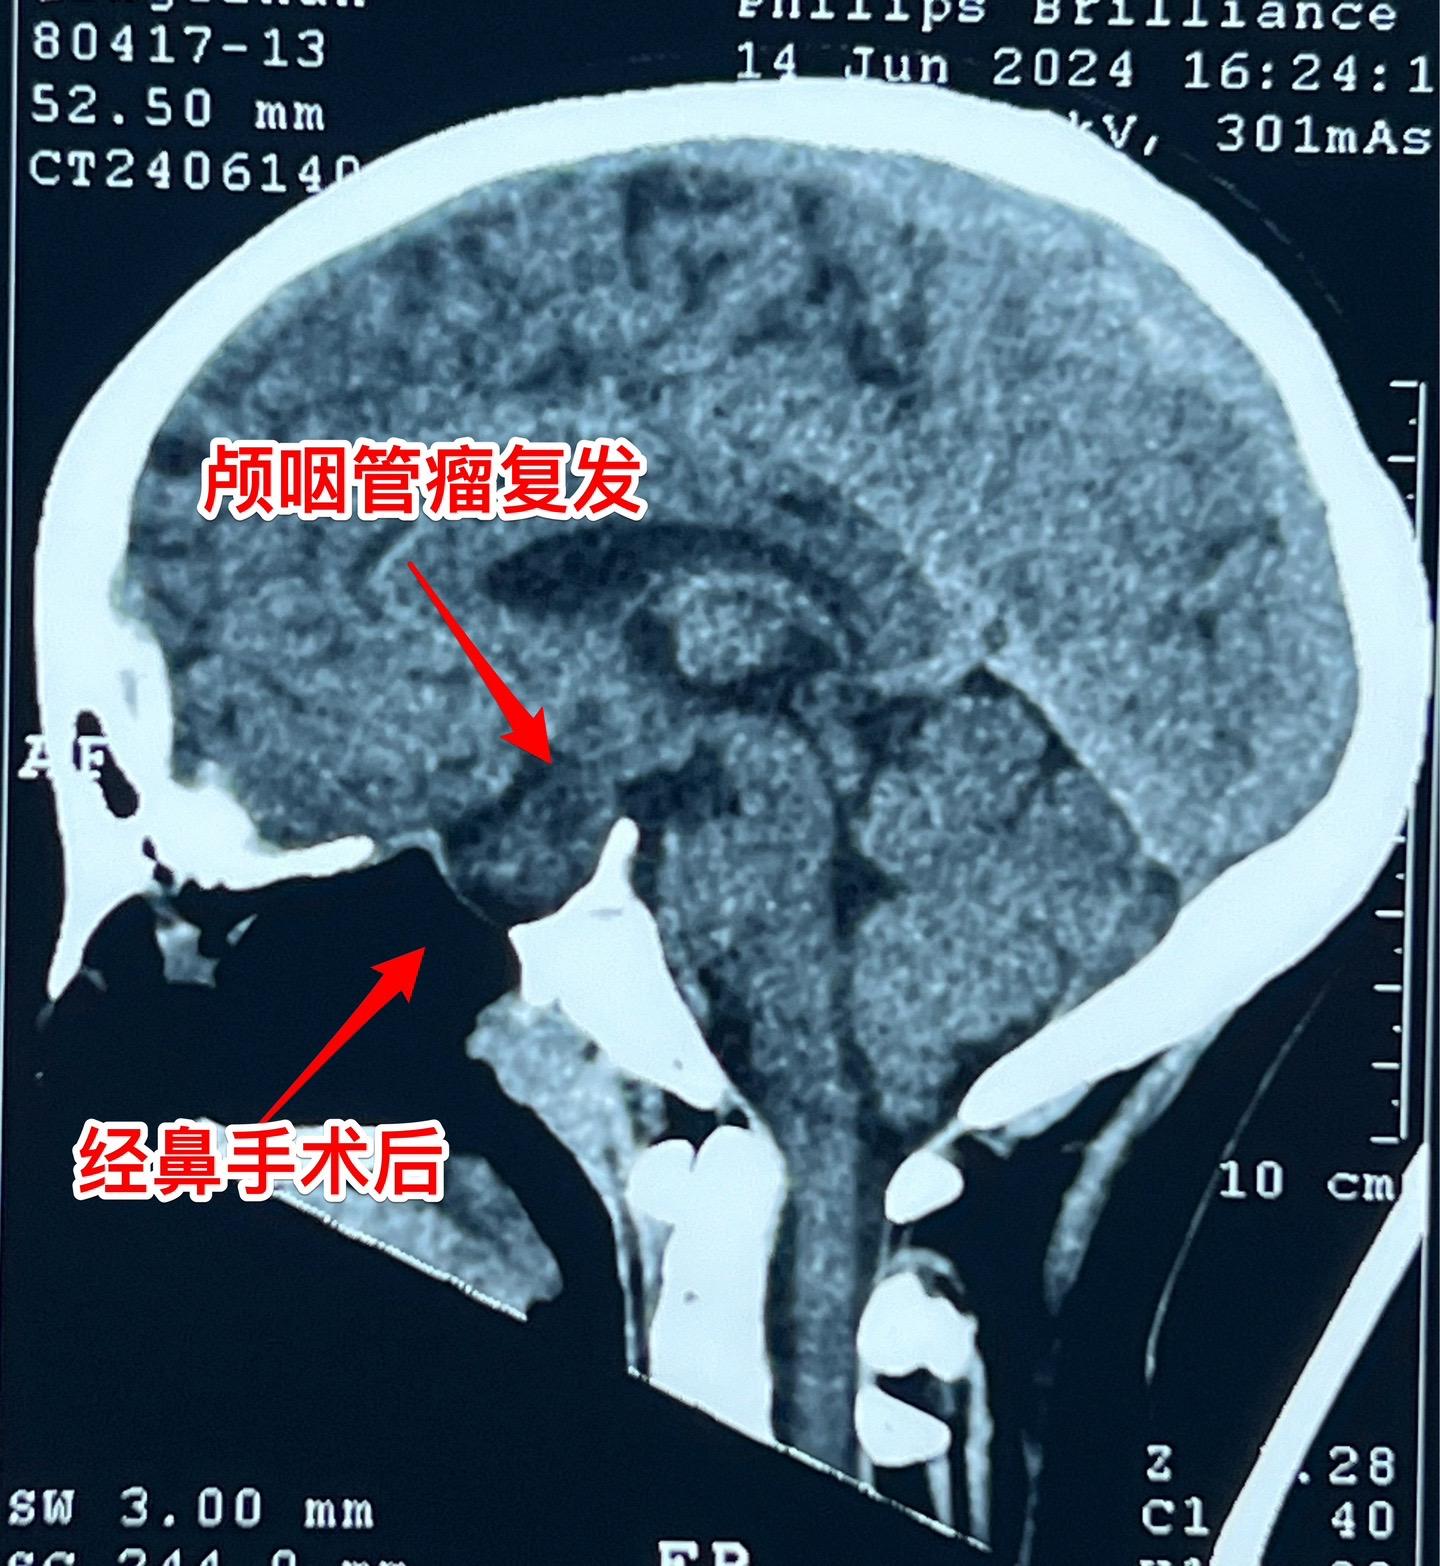

颅咽管瘤复发,病人该如何面对?11岁四川女孩子,颅咽管瘤复发了! 距离第一次经鼻内镜手术不到一年时间,颅咽管瘤就复发了,右眼视力下降。所以只能再次手术 近3年时间内我们科遇到的经鼻手术后复发的颅咽管瘤病例数呈显著增长趋势。在2024年完成的90例颅咽管瘤中,经鼻手术后复发者占比为12.2%。 这个增长趋势与近年来中国开展经鼻内镜手术切除颅咽管瘤例数的增长趋势是一致的。 4月21日我们作了开颅手术,将肿瘤完全切除了。 颅咽管瘤是神经外